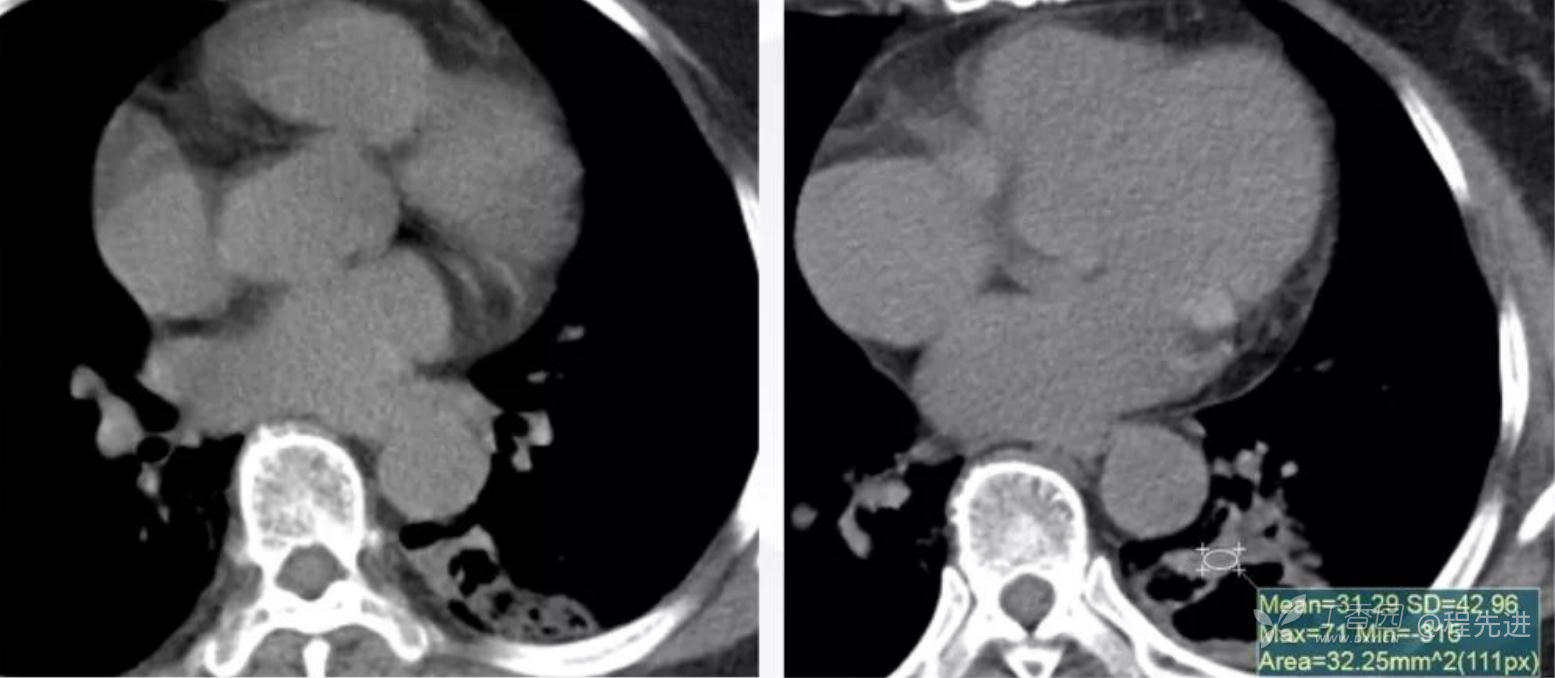

纵隔窗平扫